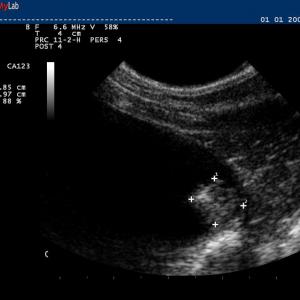

Auch in der Veterinärmedizin wird das schonende Verfahren der Ultraschalldiagnostik zunehmend eingesetzt. Wir verwenden es im Bereich der Abdominal- und Trächtigkeitsdiagnostik .